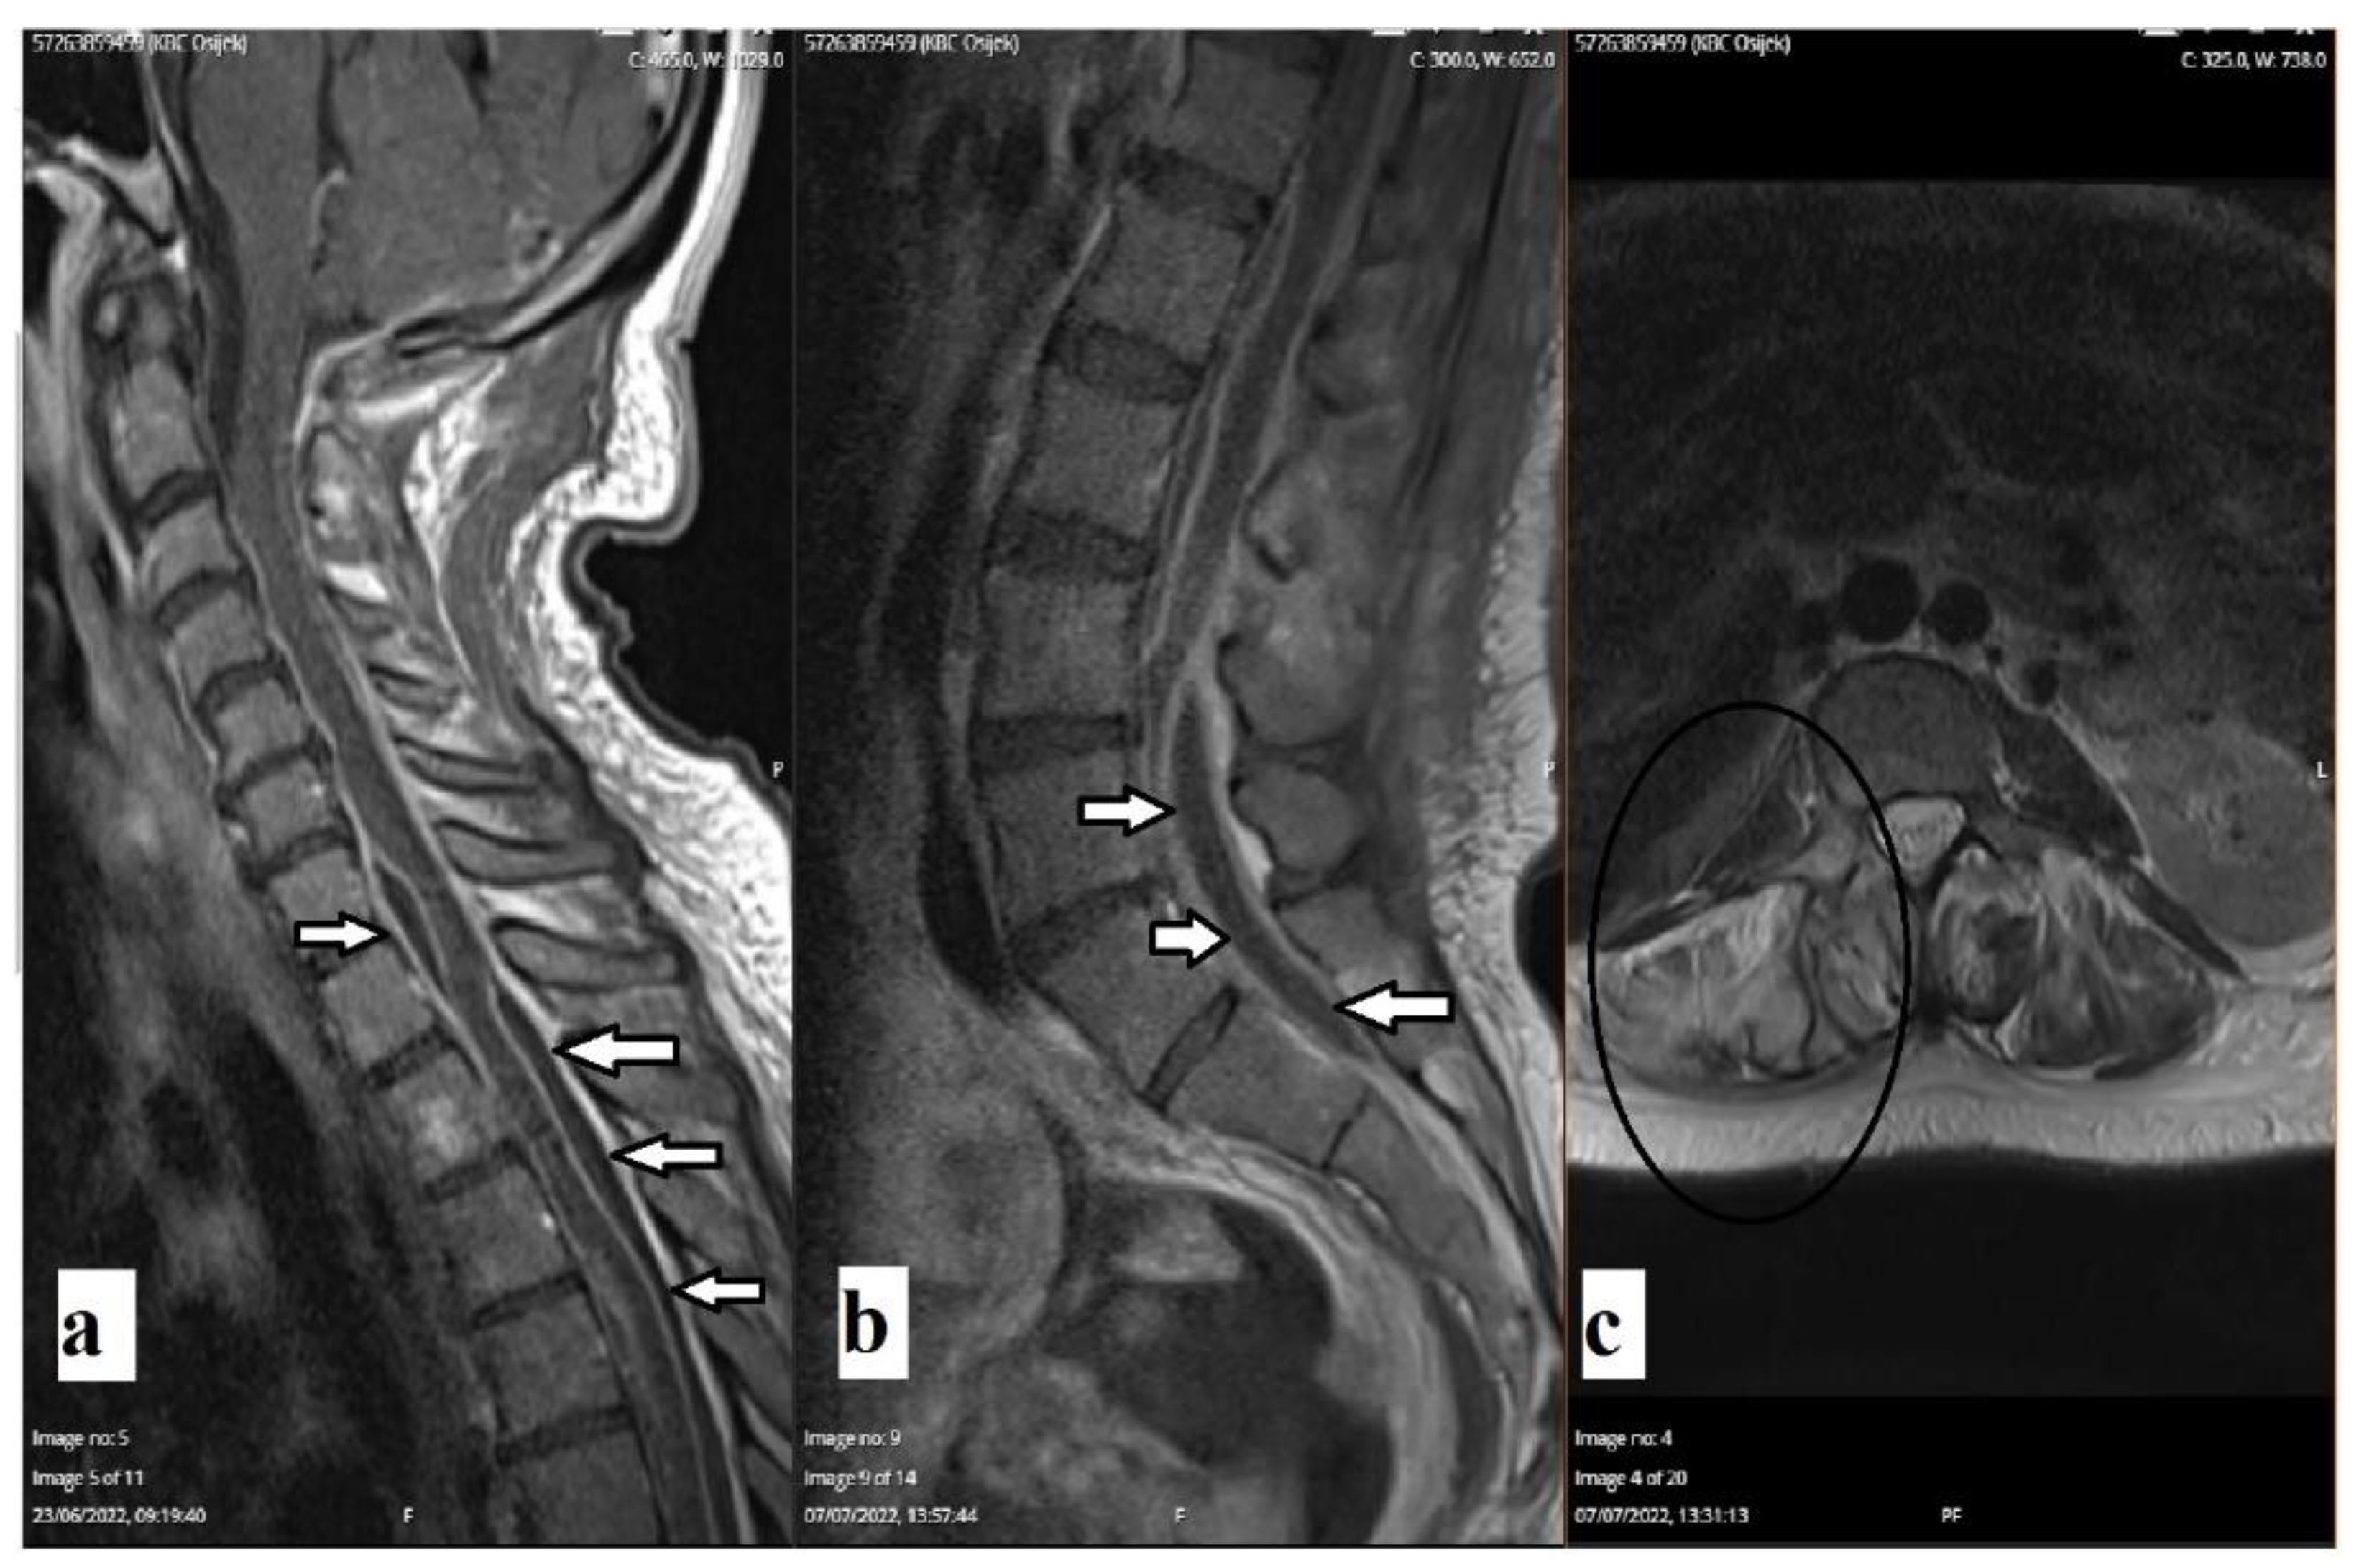

A follow-up CT scan of the brain revealed the complete resorption of previously described gas inclusions. The follow-up magnetic resonance imaging (MRI) of the whole spine revealed encapsulated purulent content along the thoracic medulla, cauda equina, and hyperintense signal on the T2-weighted image of the right-sided pedicle of the L3 vertebra (Figure 3). A follow-up laboratory examination one month after discharge revealed completely normal findings.

Figure 3. Enhanced sagittal T1-weighted MRI scans of the cervical and thoracic spine (a,b) revealed encapsulated purulent content along thoracic medulla and cauda equina (arrows). An axial T2-weighted MRI scan (c) revealed hyperintensity of the right-sided pedicle of the vertebra L3 and paravertebral soft tissue (oval).